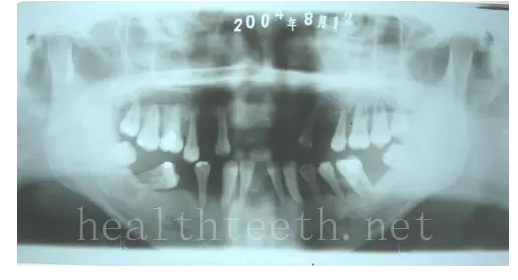

左上乳3滯留,恒3未見萌出,曲面斷層片顯示牙齒埋伏